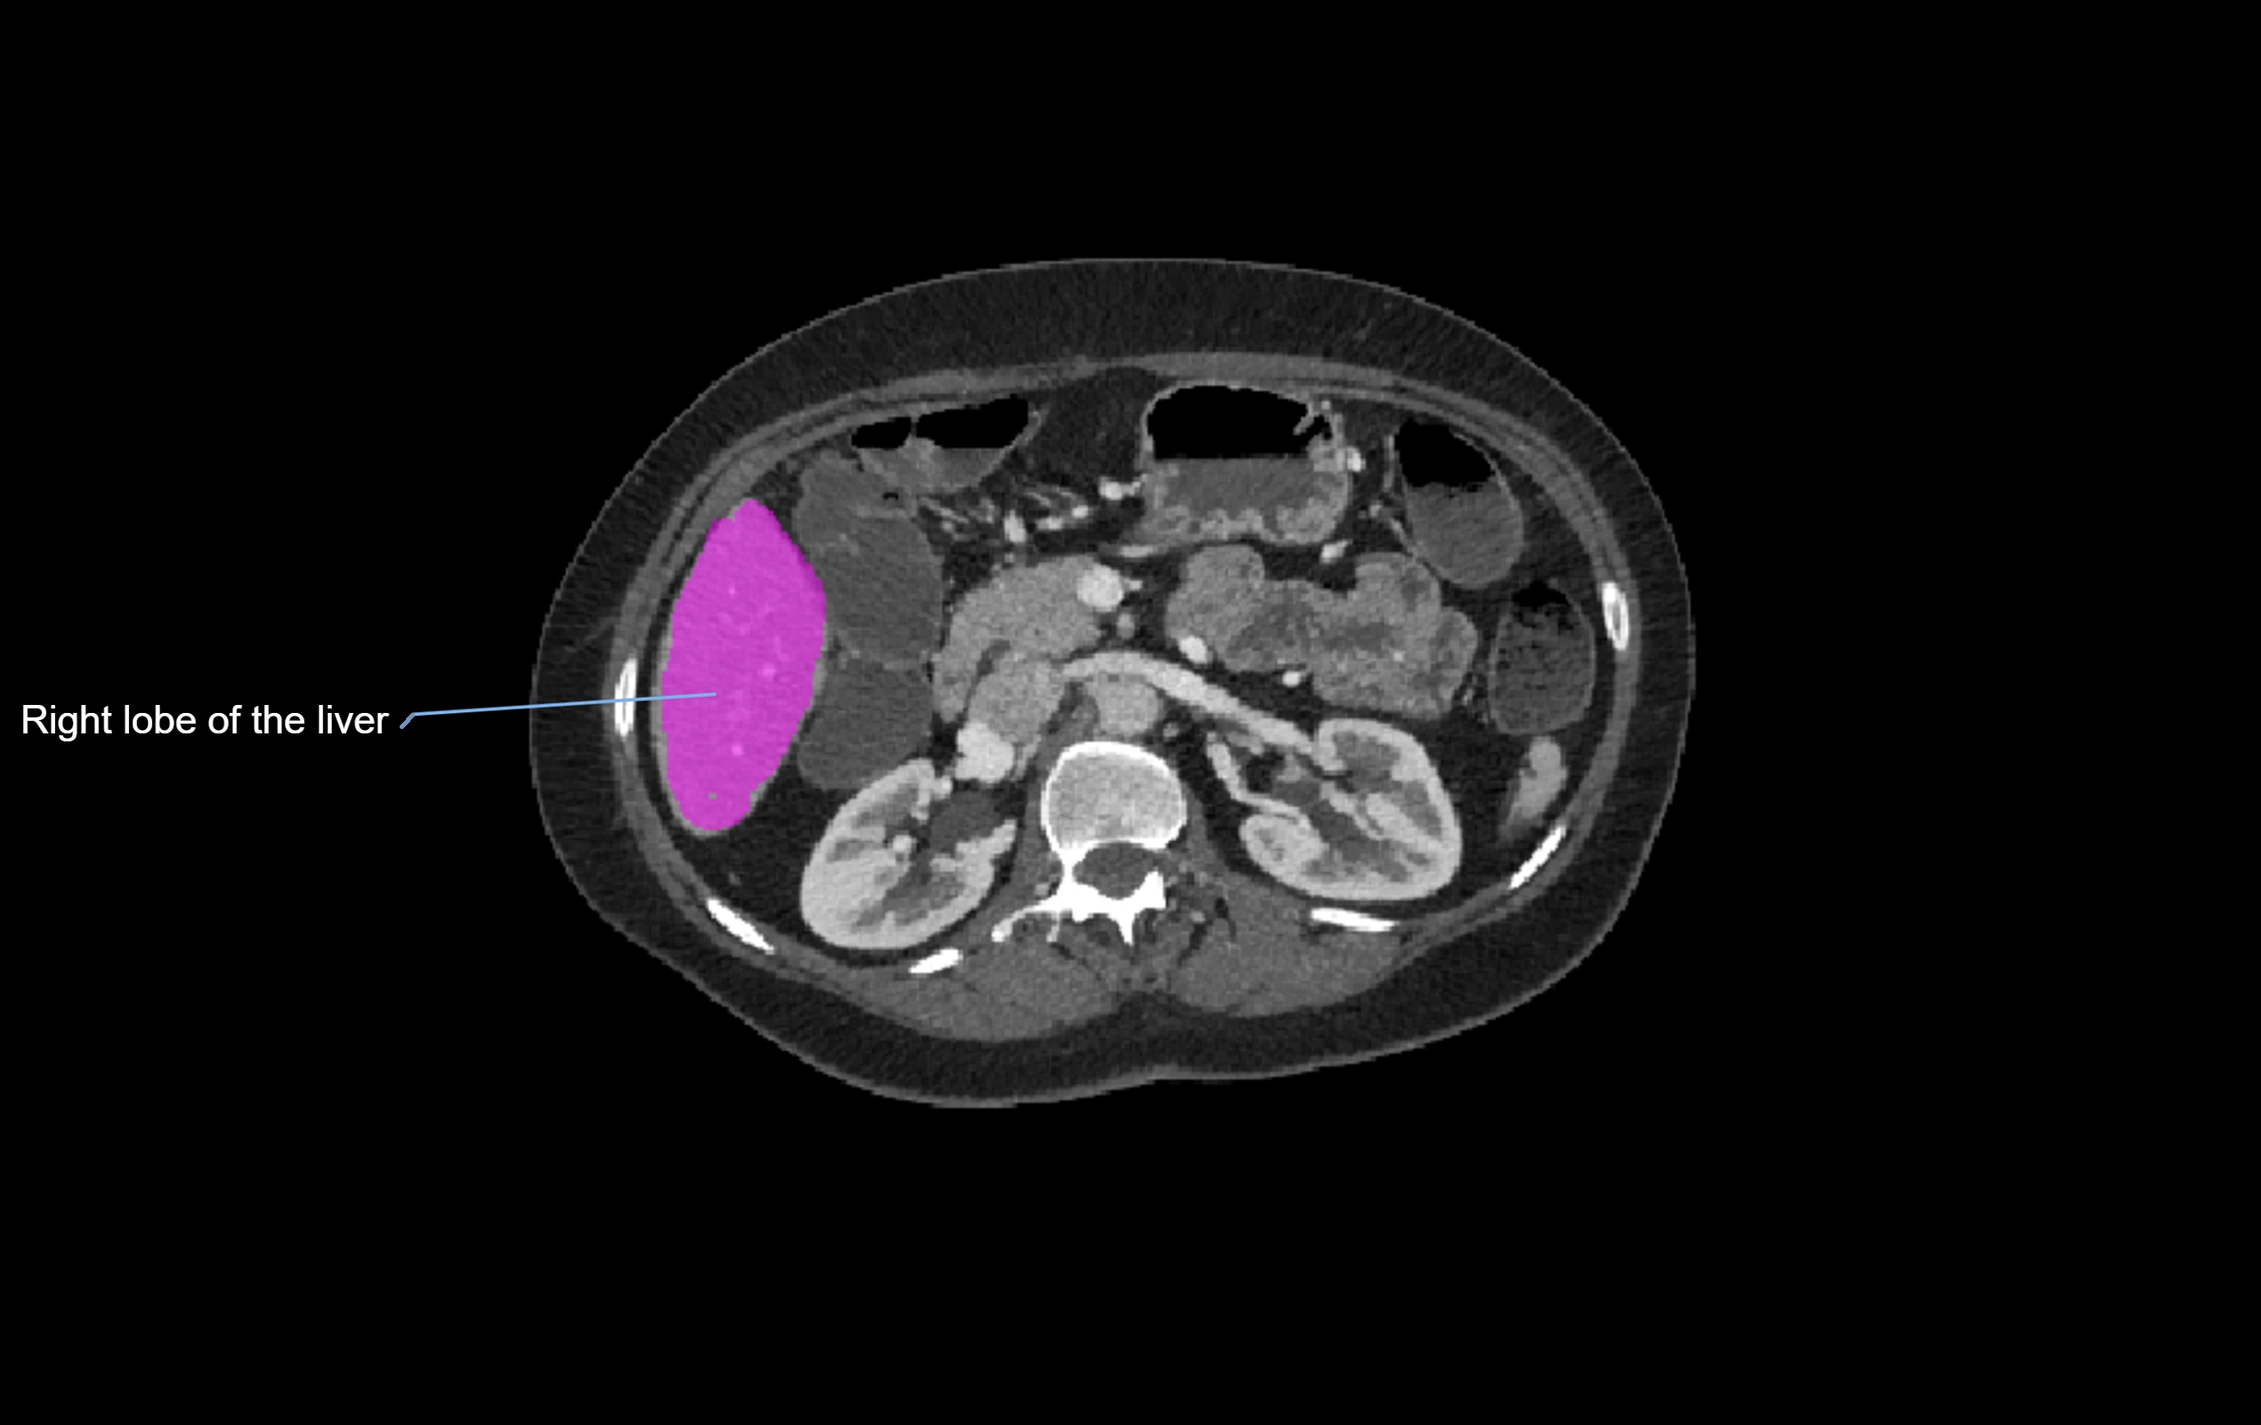

CT Image

image